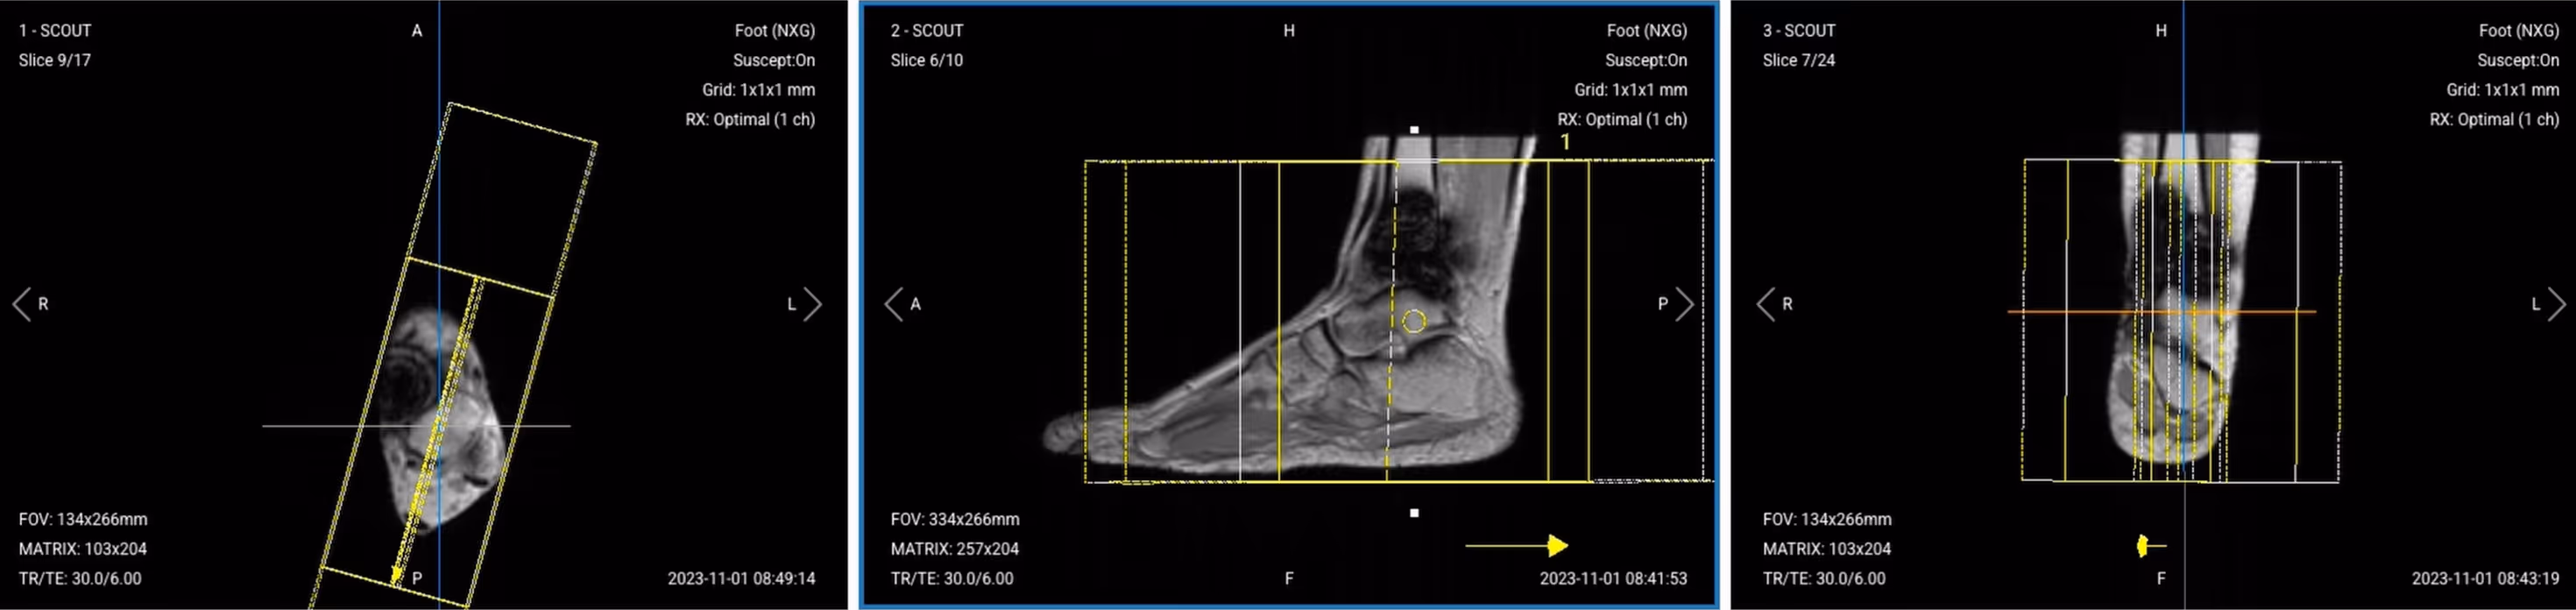

3. Coronal PD STIR TSE

Correct Planning:

Correct slice planning of Coronal PD STIR TSE

Planning Instructions:

• Use the lateral and medial malleoli as your anatomical references.

• Align the slices as follows:

• Axial localizer: Ensure slices are parallel to the malleoli.

• Sagittal localizer: Angle slices parallel to the tibial bone and center the slice package and angle the slices parallel to the tibial bone.

• Coronal localizer: Center the slice package.

• Use appropriate geometry parameters:

• Slice number: Cover the ankle from anterior to posterior (25–30 slices).

• Slice thickness: 3 mm for consistent resolution.

• Slice gap: 0.3 mm to maintain continuity.

• Set the fold-over direction (phase encoding) to right–left (RL) since no anatomy extends outside FOV in this direction.